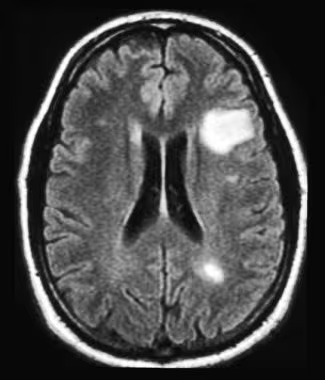

The diagnosis of Multiple Sclerosis (MS) typically involves a combination of reviewing medical history, conducting a neurological examination, and performing various tests. Magnetic resonance imaging (MRI) scans of the brain and spinal cord play a crucial role in identifying specific lesions that indicate MS. Analysis of cerebrospinal fluid, obtained through a lumbar puncture such as Spinal Tap, may reveal increased levels of certain proteins associated with inflammation and demyelination. Evoked potential tests, which measure the brain's electrical activity in response to stimuli, can help identify abnormalities in nerve transmission. Additionally, the clinical symptoms and their progression over time are vital factors in diagnosing MS. It is essential to conduct a comprehensive evaluation that integrates these assessments to ensure an accurate diagnosis and initiate appropriate management strategies for individuals suspected of having MS.